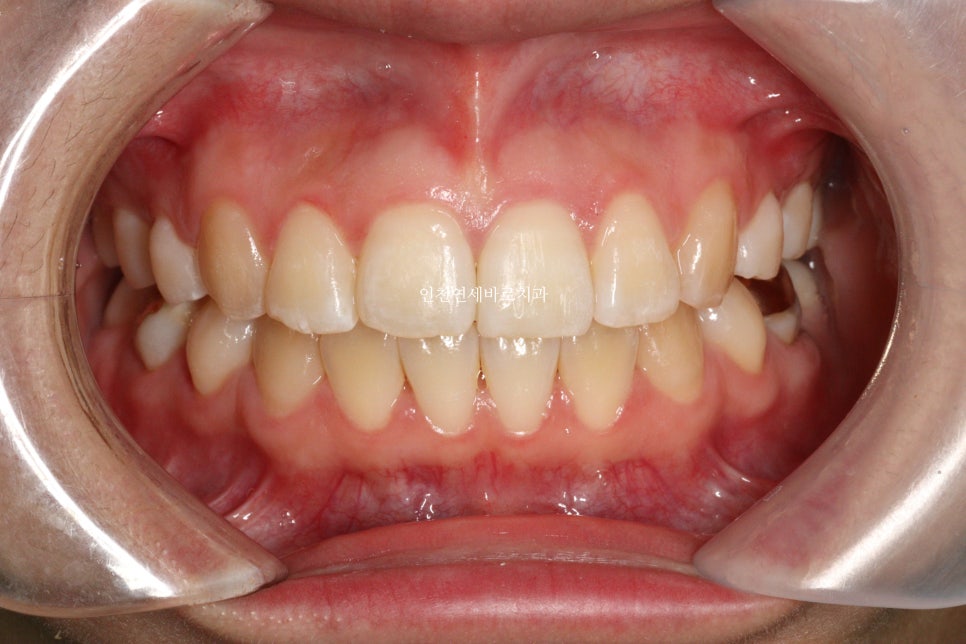

오늘은 교정이 끝난지 오래되어 재교정을 하고 싶어 내원했던 환자분 이야기 입니다.

예전에 중학생때 발치교정치료를 받았다고 합니다.

환자분의 나이는 이제 30대

약 15년만에 다시 교정치료를 결심하셨다고 합니다.

결혼을 앞둔 분이었고

앞니하나가 많이 틀어졌는데 점점 틀어진다고 하셨습니다.

철사 유지장치를 붙여놨었는데 오래전에 탈락 하고 다시 붙이지 않으셨다고 합니다.